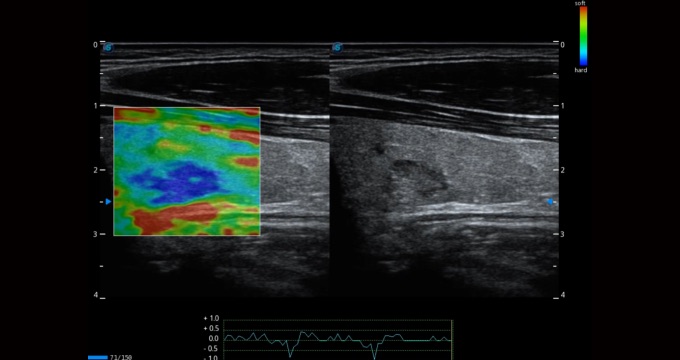

彈性成像支持多把探頭,滿足全面的臨床應(yīng)用。無需高頻度外力作用可真實(shí)反映組織的形變,具有良好的重復(fù)性,幫助醫(yī)生早期洞察潛在的病理學(xué)特征。